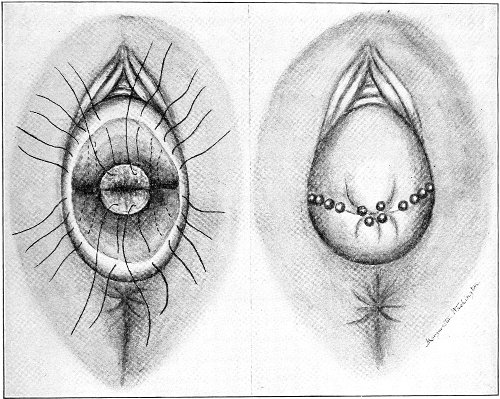

The secondary operation is performed at any time after cicatrization has occurred—often many years after the receipt of the injury. This operation is at present one of the commonest in gynecology, because the injury is not detected, is neglected, or is improperly repaired after labor. In the secondary operation an anesthetic is necessary. The mucous membrane must be removed or denuded on the posterior wall and about the mouth of the vagina, in order that the lacerated structures may be brought again in apposition. The denudation is best made by means of scissors curved on the flat (Figs. 24 and 25).

The strip of mucous membrane to be removed is picked up with a tenaculum (Fig. 26) or with tissue forceps 65 (Fig. 27); the scissors are placed with the blades parallel to the surface to be denuded, and the strip is cut away evenly, in one piece if possible. A similar contiguous strip is removed, and so on until the necessary surface is bare. Sponges in holders (Fig. 28) or continuous irrigation may be used to remove blood.

Silver wire and silkworm gut are the best sutures in the operation of perineorrhaphy.

The suture is conveniently attached to the needle by means of a silk carrier (Fig. 31).

The sutures may be fastened by passing the ends through a perforated shot which is slipped down to the line of union and compressed by the shot-compressor (Fig. 32). All blood should be carefully removed from the surfaces that are brought together. The sutures should only be sufficiently tense to produce accurate apposition. A light gauze drain should be introduced in the vagina, and should be removed in forty-eight hours. Afterward one vaginal douche of about a quart of warm bichloride solution (1:2000) should be administered every day. After the douche the labia should be separated and the vagina carefully dried by cotton held in dressing-forceps. Except in those cases in which the sphincter ani is involved, the bowels may be moved on the second or third day. The woman should stay in bed for two weeks, at the end of which time the sutures should be removed. 67 She should avoid heavy lifting, long standing, and bicycle- or horseback-riding for two months after the operation. Constipation should always be avoided. Coitus may be resumed six weeks after operation.